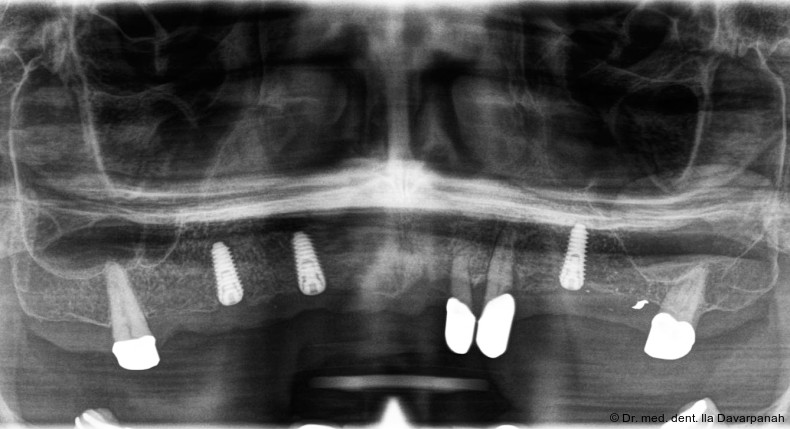

Die Implantation erfolgte navigiert mit einer Bohrschablone. Zur Optimierung der Ästhetik wurden im Frontzahnbereich bewusst keine Implantate gesetzt (Abb. 5). Nach Einheilung und Freilegung der Implantate begann die prothetische Phase (Abb. 6).

Die definitive Prothese konnte im dritten Behandlungstermin problemlos eingegliedert werden. Es waren lediglich minimale okklusale Anpassungen erforderlich (Abb. 20–24).